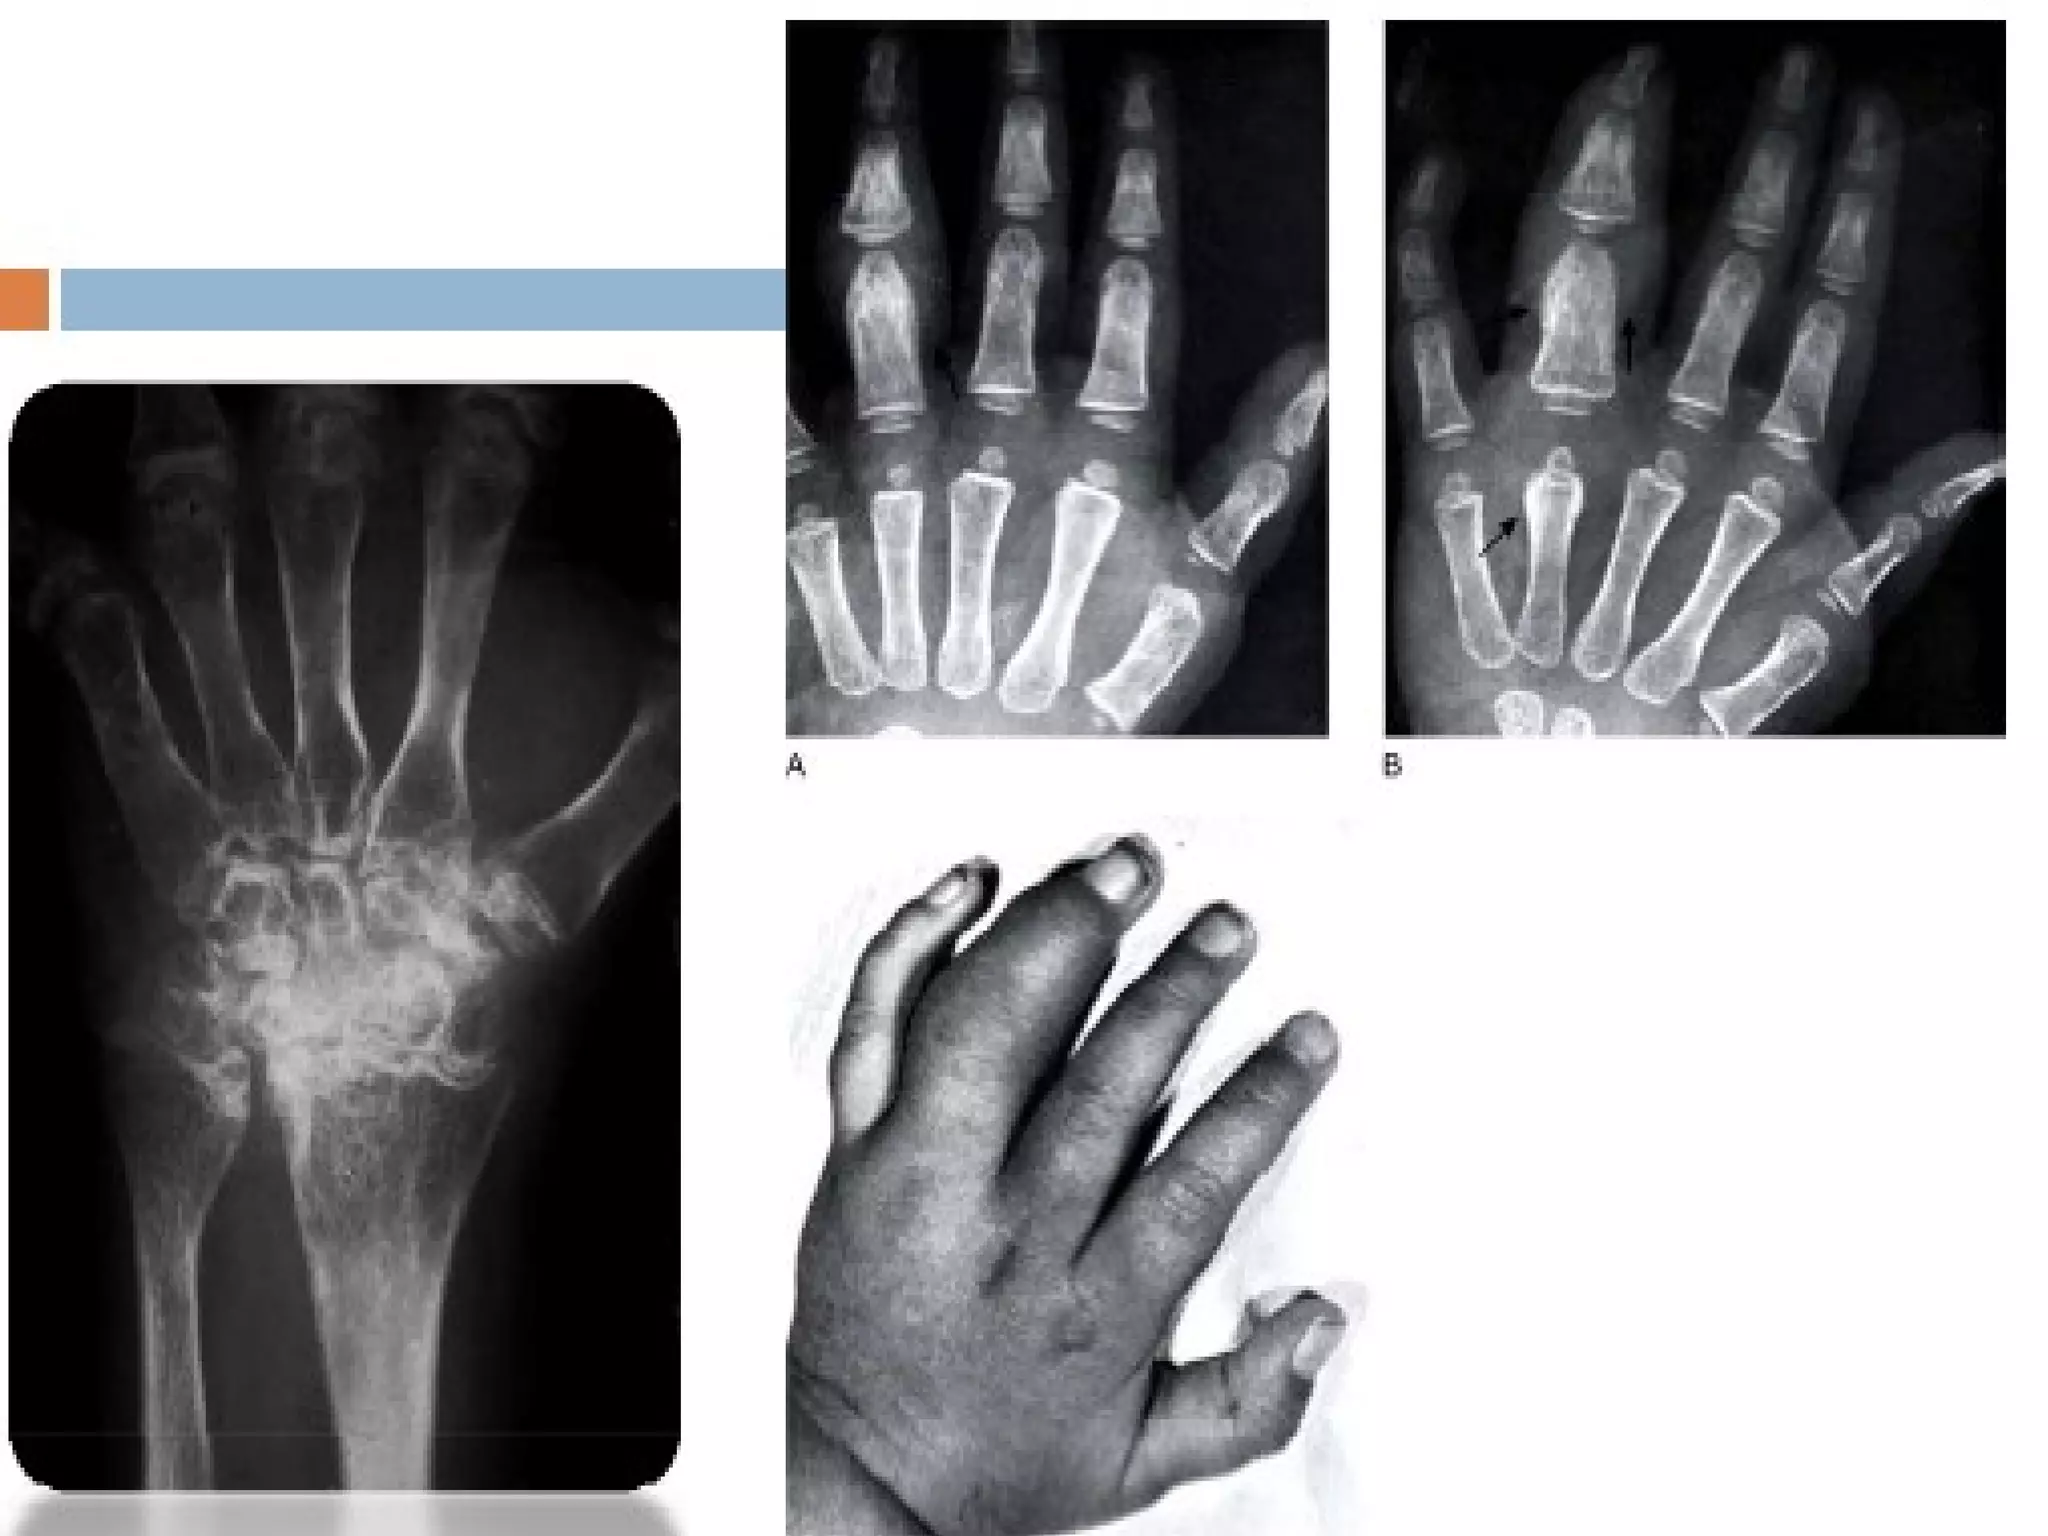

Par ailleurs, la douleur et l’inflammation des tendons empêchent les muscles qui protègent l’articulation de travailler suffisamment. Ce qui les affaiblit et diminue leur volume, on parle alors d’atrophie musculaire. L'évolution de l'atteinte articulaire est visible sur les clichés radiologiques. Au premier stade de la maladie, la radio permet simplement de voir le gonflement de l’articulation. À des stades plus avancés de la maladie, la destruction du cartilage est visible du fait du pincement de l’interligne articulaire (amincissement ou disparition de l’espace qui sépare les deux éléments de l’articulation). L’évolution de la maladie est très variable, longue et souvent imprévisible. Le passage d’une forme à l’autre est possible dans certains cas.